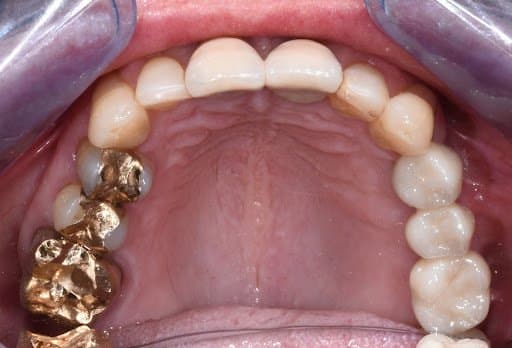

Occlusal view of initial clinical situation

Final photo documentation post-cementation

After three months, the implants were exposed. One week after uncovering, an impression of the implants was taken using a closed tray (double mix: Detaseal hydroflow putty + lite) and was sent to the laboratory to digitize the case and fabricate the final zirconia bridge.

The bridge was delivered to the practice and cemented to the implants with Fuji PLUS Powder-Liquid (GC). The patient had follow ups for 12 months after the cementation, she was free of pain and very satisfied with the bridge.